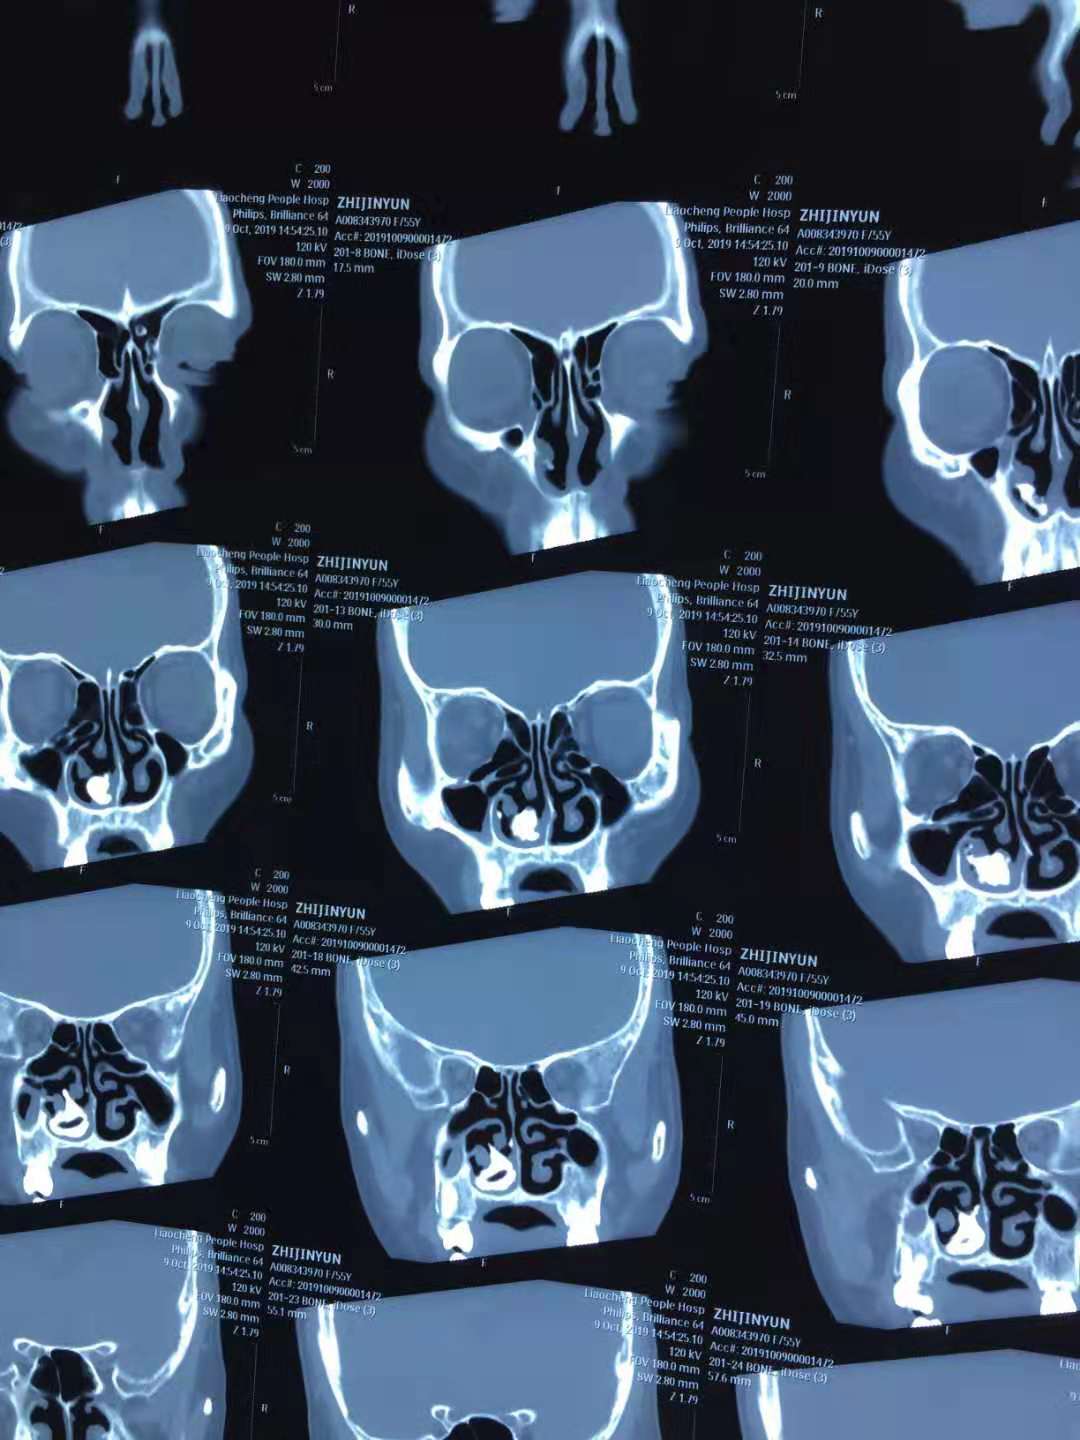

CT检查诊断为:鼻窦炎、右侧鼻腔占位。于10月11日来聊城市退役军人医院耳鼻喉科就诊,鼻内镜检查诊断为“鼻石(右)”,至此困扰病人10多年的口臭终于找到原因了。因病人患有冠心病,经积极术前准备,于2019年10月14日上午在气管插管全麻鼻内镜下行右侧鼻石取出术。术中发现鼻石呈不规则状,自前鼻孔沿下鼻道、鼻底、总鼻道达后鼻孔,部分分支深入中鼻道及嗅裂区,包绕部分下鼻甲及中鼻甲,整体取出困难。术中以异物钳夹碎鼻石,分次全部取出,手术过程顺利。